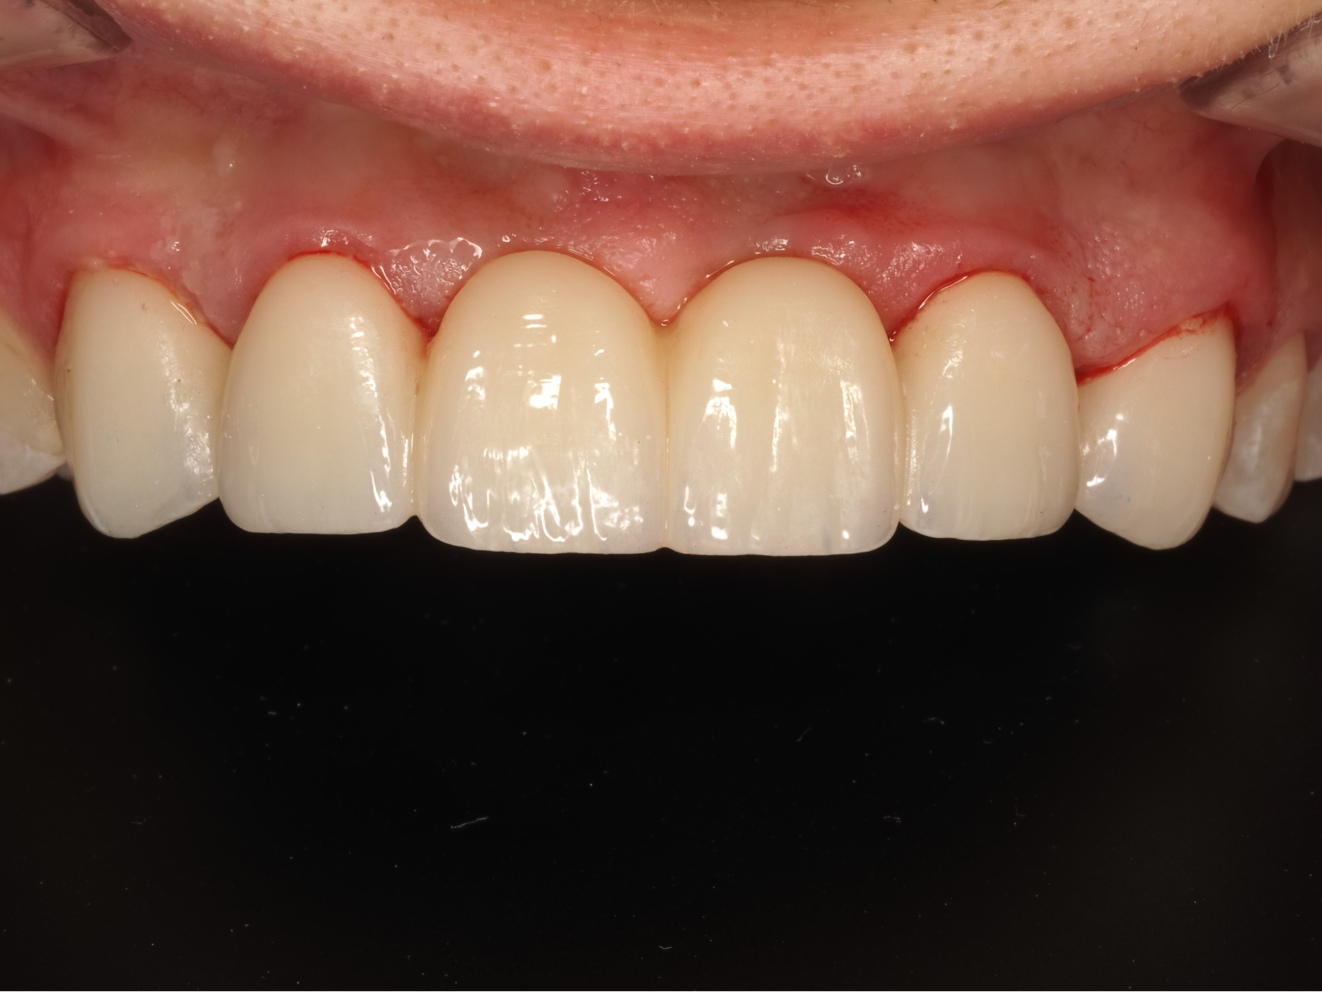

*Efekty zabiegów przedstawione na zdjęciach są rezultatem indywidualnego procesu leczenia i mogą być różne u innych osób.

*Zdjęcia 'przed i po' mają charakter informacyjny i ilustrują potencjalne rezultaty zabiegów.

*Prezentowane zdjęcia przedstawiają efekty wybranych zabiegów u konkretnych pacjentów i mają charakter poglądowy. Efekty leczenia mogą się różnić w zależności od indywidualnych uwarunkowań.